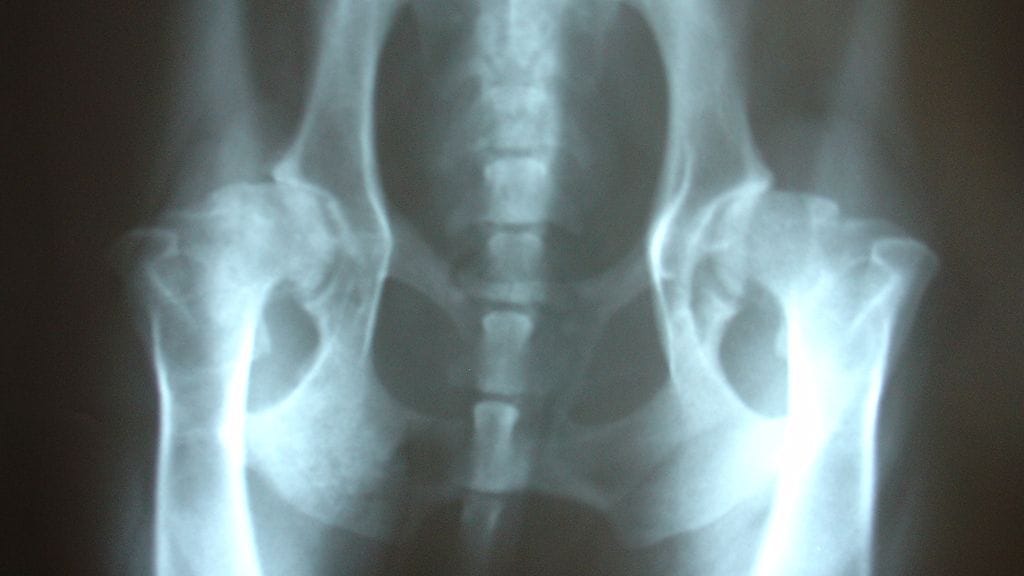

Espoo on pyörittänyt menestyksekkäästi lonkkamurtumapotilaille tarkoitettua lonkkaliukumäkeä kaksi ja puoli vuotta. Lonkkamurtumasta kuntoudutaan erittäin nopeasti verrattuna maan keskiarvoon.

– Valtakunnallinen keskiarvo on 46 päivää, me pääsemme tästä puoleen. Ja olennaista on se, että tämän 23 päivän jälkeen meidän potilaat ovat paremmassa kunnossa kuin keskimäärin 46 päivän jälkeen, sanoo Louhija.